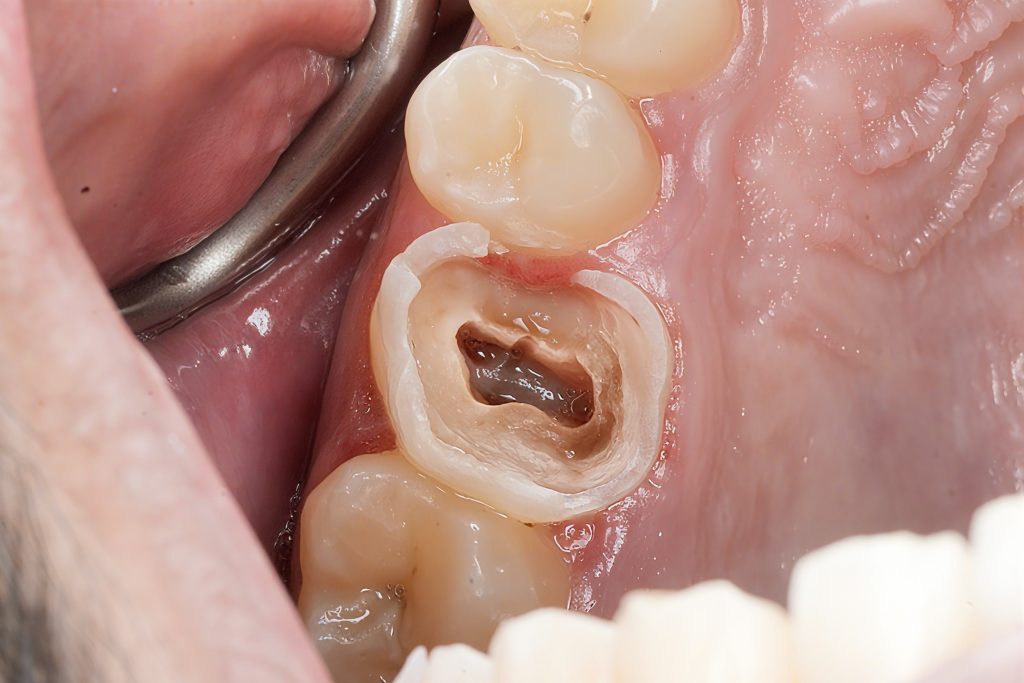

Removal of Old Restorations & Caries

After cleaning, a deep proximal margin was revealed—subgingival and not suitable for direct composite.

This indicated the need for Deep Margin Elevation (DME) to bring the margin supragingival.